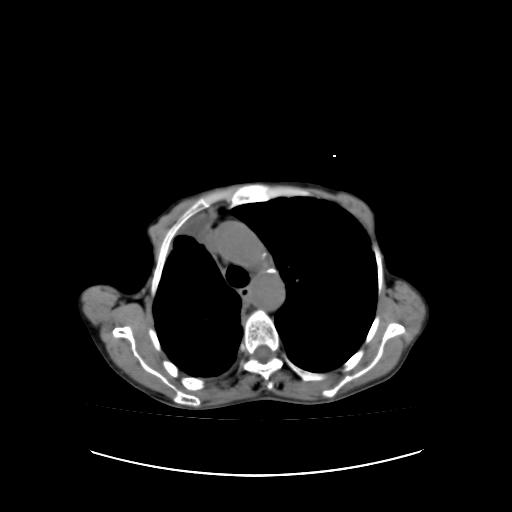

标题: CT16930:女 59 胸痛6个月 胸水脱落细胞学见瘤细胞 [打印本页]

可见多发肺内病灶,且胸膜病灶较多有圆球状而非丘状,多考虑胸膜转移瘤伴胸腔积液,右侧胸廓缩小固定,且部分病灶呈丘状,尚不除外恶性胸膜间皮瘤伴肺内转移

右侧胸膜增厚,局部呈结节状增厚,右侧胸腔少量积液。双肺未见确切肿块影。纵隔未见淋巴结肿大。气管、支气管通畅。考虑右侧胸膜间皮瘤(恶性?)可能性大。不除外癌性胸膜炎。

符合:恶性胸水的表现。多考虑恶性胸膜间皮瘤。

右侧胸廓塌陷,右侧胸膜广泛增厚并见多发胸膜结节,右侧少量胸腔积液并包裹。

右侧广泛胸膜增厚,局部呈结节状增厚,右侧胸腔少量积液。双肺未见确切肿块影。纵隔未见淋巴结肿大。气管、支气管通畅。考虑右侧胸膜间皮瘤(恶性?)可能性大。支持!

胸膜转移瘤  包裹性胸腔积液  肺内转移